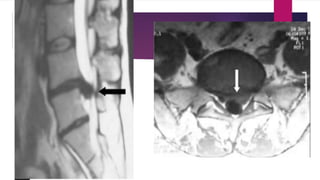

HERNIA DISCAL

 La hernia discal se valora con la

TAC y se caracteriza por una

formación de disco hiperdensa

fuera de su ubicación normal.

 En función de la orientación

anómala que tome el disco

podemos dividirla en: Hernia

discal central: Cuando el disco

está en el centro comprimiendo

la médula.

HERNIA DISCAL  Lahernia discal se valora con la TAC y se caracteriza por una formación de disco hiperdensa fuera de su ubicación normal.  En función de la orientación anómala que tome el disco podemos dividirla en: Hernia discal central: Cuando el disco está en el centro comprimiendo la médula.